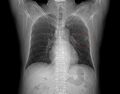

1. X-RAY 촬영. 전면 및 측면 두 장